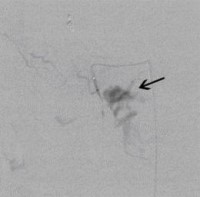

Postoperative abdominelle Blutungen bei chronischer Pankreatitis (Pfeile: Art. hepatica und Art. gastroduodenalis).

(Bild 1 von 5)

Postoperative abdominelle Blutungen bei chronischer Pankreatitis vor Embolisation der Art. gastroduodenalis mittels Metallspiralen (Coils)

(Bild 2 von 5)